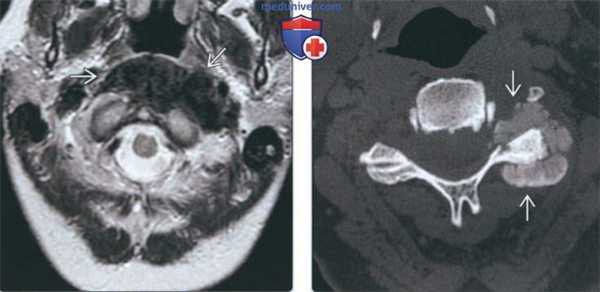

(Слева) На аксиальной МРТ (Т2 ВИ) спереди от срединного атланто-аксиального сустава определяется гипоинтенсивное объемное образование со слегка бугристыми, но четко очерченными краями.

(Справа) На аксиальной КТ шейного отдела позвоночника без КУ вокруг дугоотростчатого сустава определяется плотный участок с бугристыми краями без мягкотканного компонента.